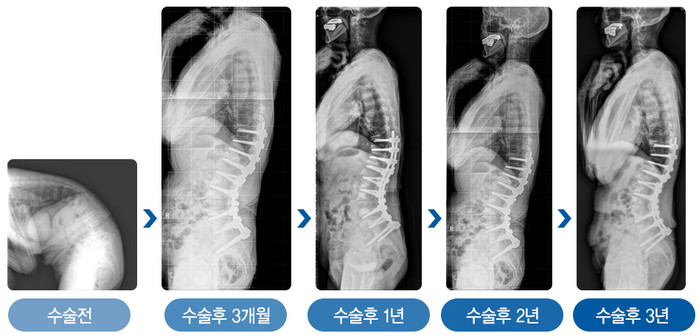

김용찬 교수팀은 전방 추체 사이 유합술과 후방기기 고정술을 병합한 새로운 수술방법을 개발했다. 기존 수술 방법에서 추가적으로 추체 사이의 전방 종인대를 함께 부분 절제하는 수술법이다. 기존 추체절골술 후에 완벽한 구현되지 못했던 생리적 허리 곡선을 최대한 구현했으며, 빈번한 불유합으로 인한 재변형에 의한 재수술 발생을 획기적으로 감소시켰다. 또 수술 직후 얻었던 허리 곡선이 오랜 기간 동안 유지됨을 확인했다.

| ▲그림1. 추체절골술과 함께 전방 추체 사이의 앞쪽 종인대를 함께 절제함으로써 노인성 후만변형 환자가 수술 후 완벽한 생리적 허리곡선을 되찾았다. |

| ▲그림2. 심한 노인성 후만변형으로 수술을 받은 78세 환자 (여)는 수술 3년 후에도 허리곡선이 잘 유지되고 있다. |